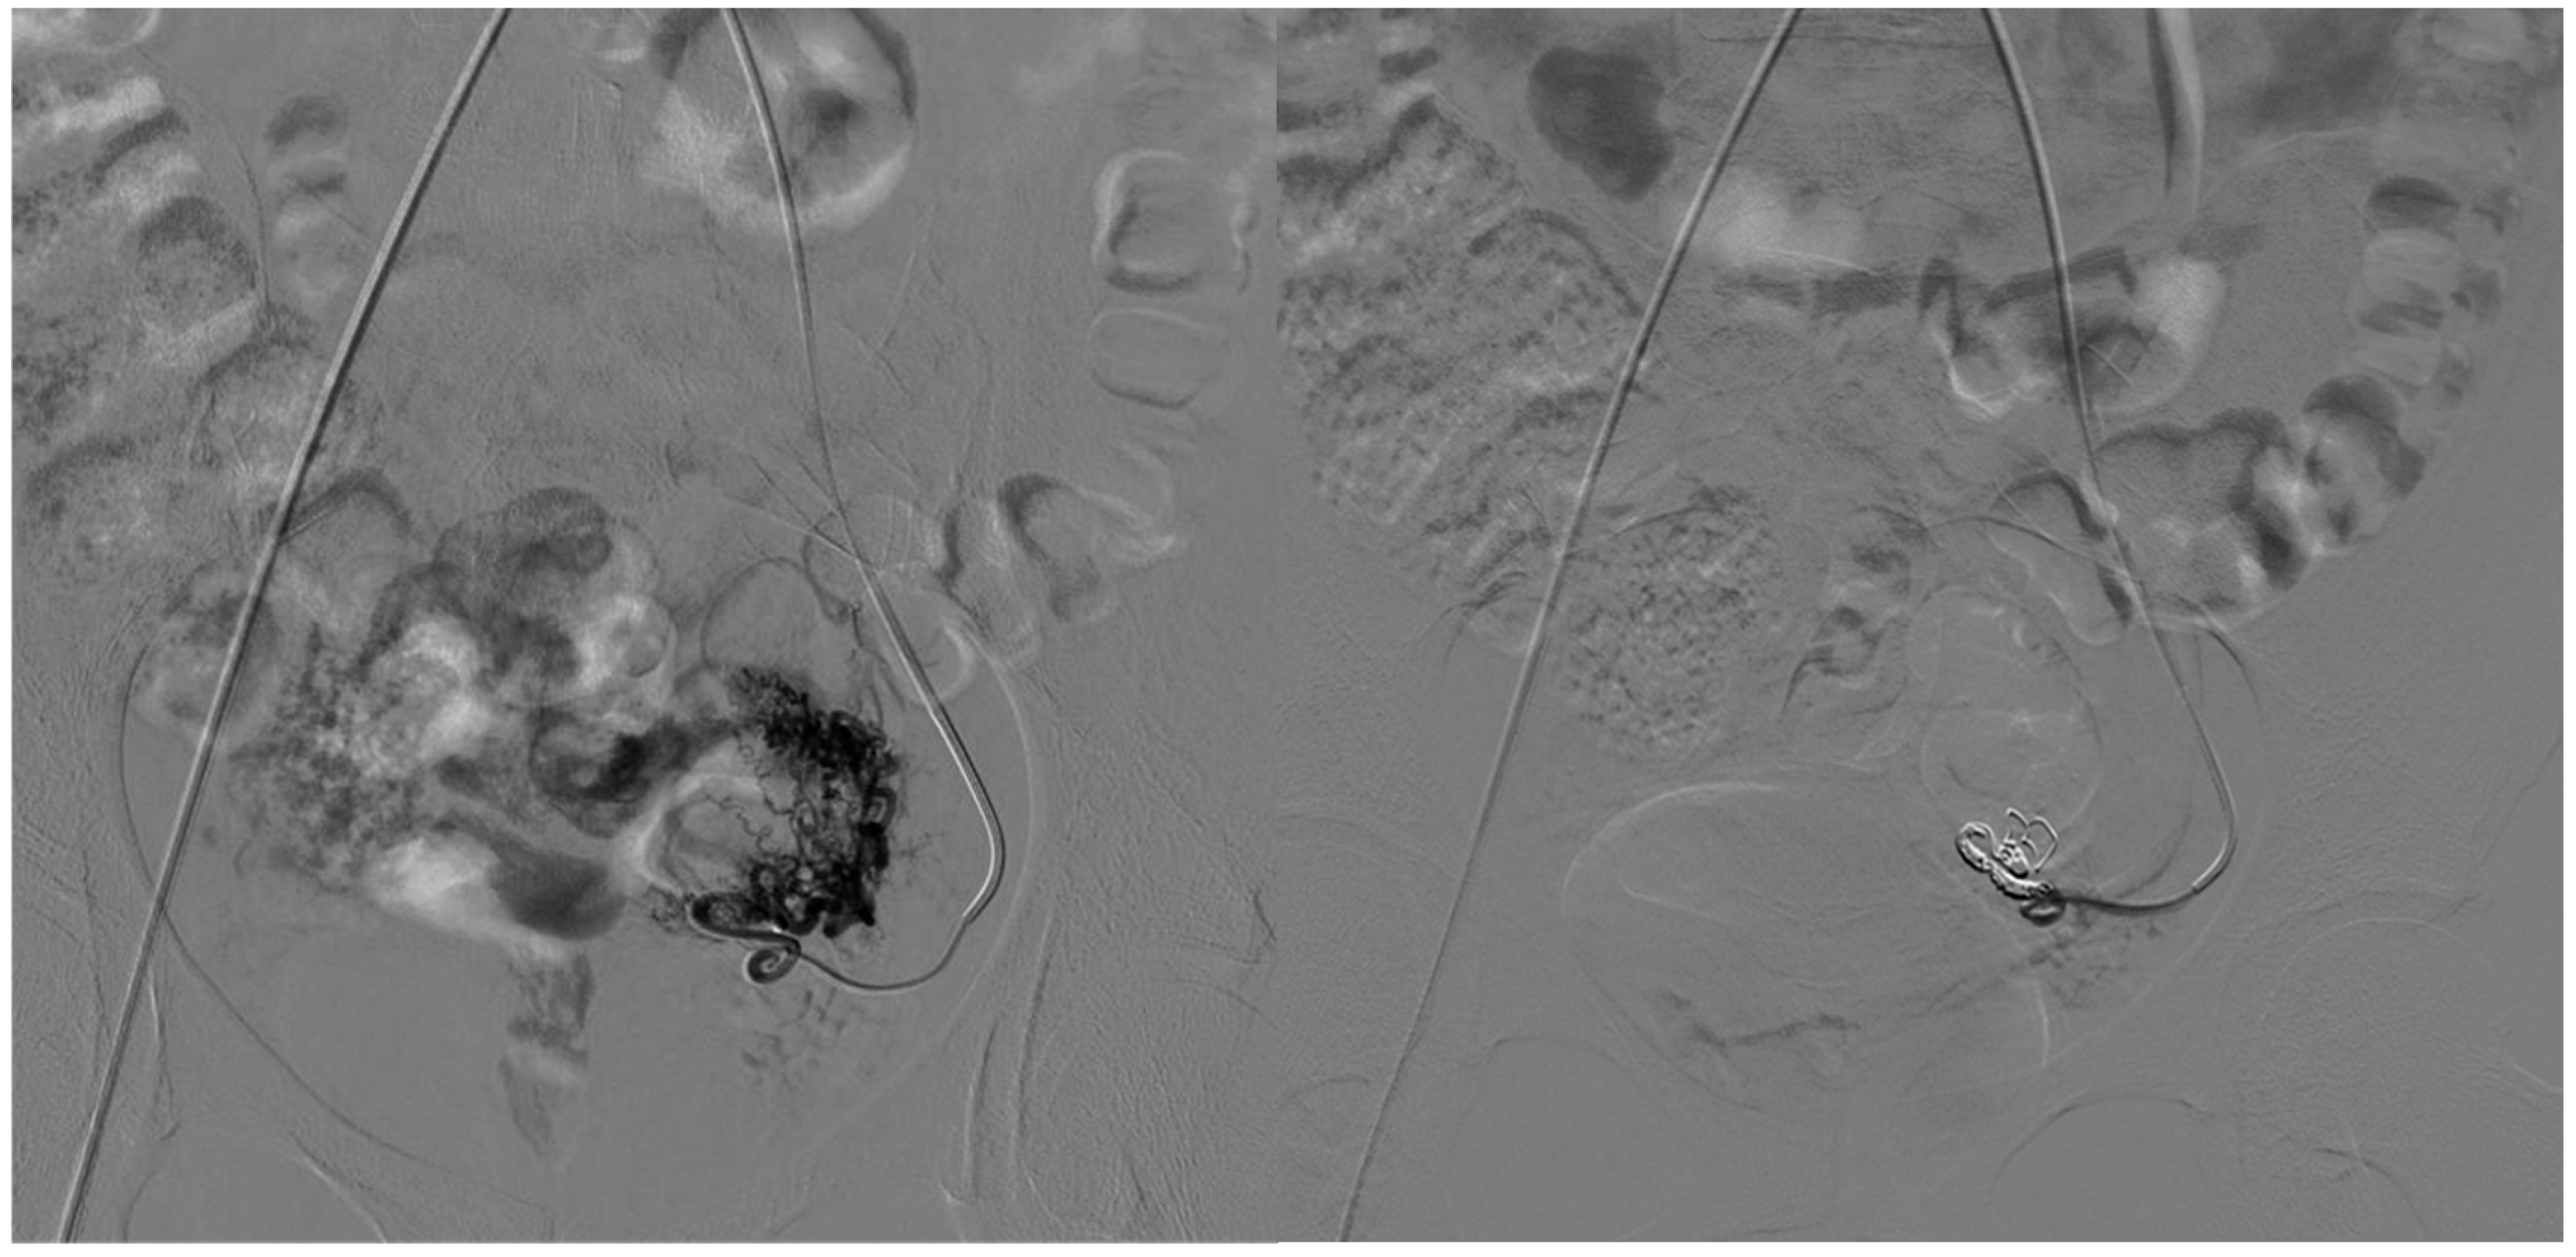

- Venous embolization was favored when the dominant outflow vein (DOV) was accessible and formed the site of arteriovenous shunting.

- Combined arterial and venous embolization was used in complex lesions with multilevel shunting, high-flow recurrence, or partial response to single-route embolization.